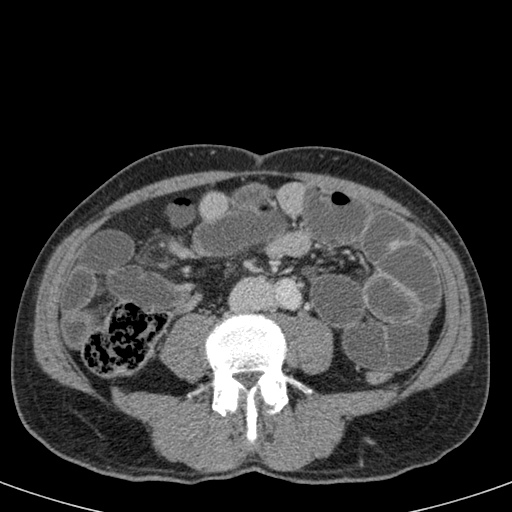

Bên trái là các hình ảnh CT bổ sung của cùng bệnh nhân nêu trên.

Hãy quan sát các hình ảnh này, tìm kiếm các dấu hiệu chính rồi tiếp tục.

Đầu tiên, chúng ta thấy đại tràng xuống xẹp và đại tràng lên không giãn, do đó đây không thể là xoắn đại tràng sigma.

Thứ hai, chúng ta thấy một cấu trúc hình mỏ chim ở góc phần tư dưới bên phải, đây là vị trí xoắn của ruột.

Ở góc phần tư dưới bên trái, chúng ta thấy manh tràng giãn.

Tái tạo ảnh mặt phẳng coronal có thể rất hữu ích trong việc thể hiện toàn cảnh tổn thương.